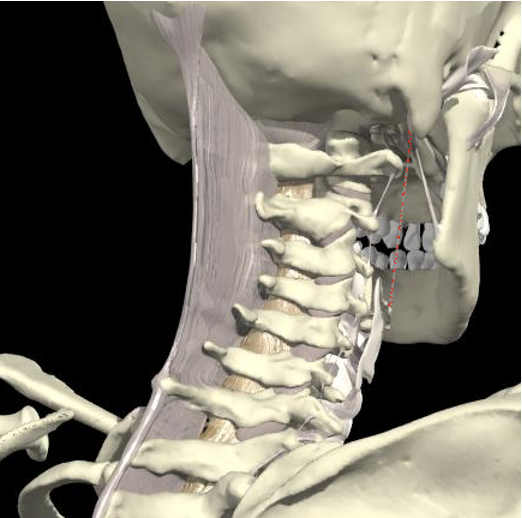

Sub-Occipital Triangle

Obliquus Capitis

Rectus Capitis

- Rectus capitis posterior major and the superior and inferior oblique muscles bound this anatomical region.

- Play a large role in the fine control of head movement.

- Involved in rotation of the head , extension or lateral flexion.

- Relations

- Vertebral Artery

- Greater Occipital nerve

Triangle between C1 transverse process (below and behind mastoid), C2 and occiput.

Pass through Trapezius, Splenius capitus (more lateral) and semispinalis capitus (more medial) to reach it.

The C2 level is a plane 2.5 cm below the mastoid process

Midway between the posterior border of the sternocleidomastoid and the dorsal midline.

Depth of 3.0-3.5 cm.